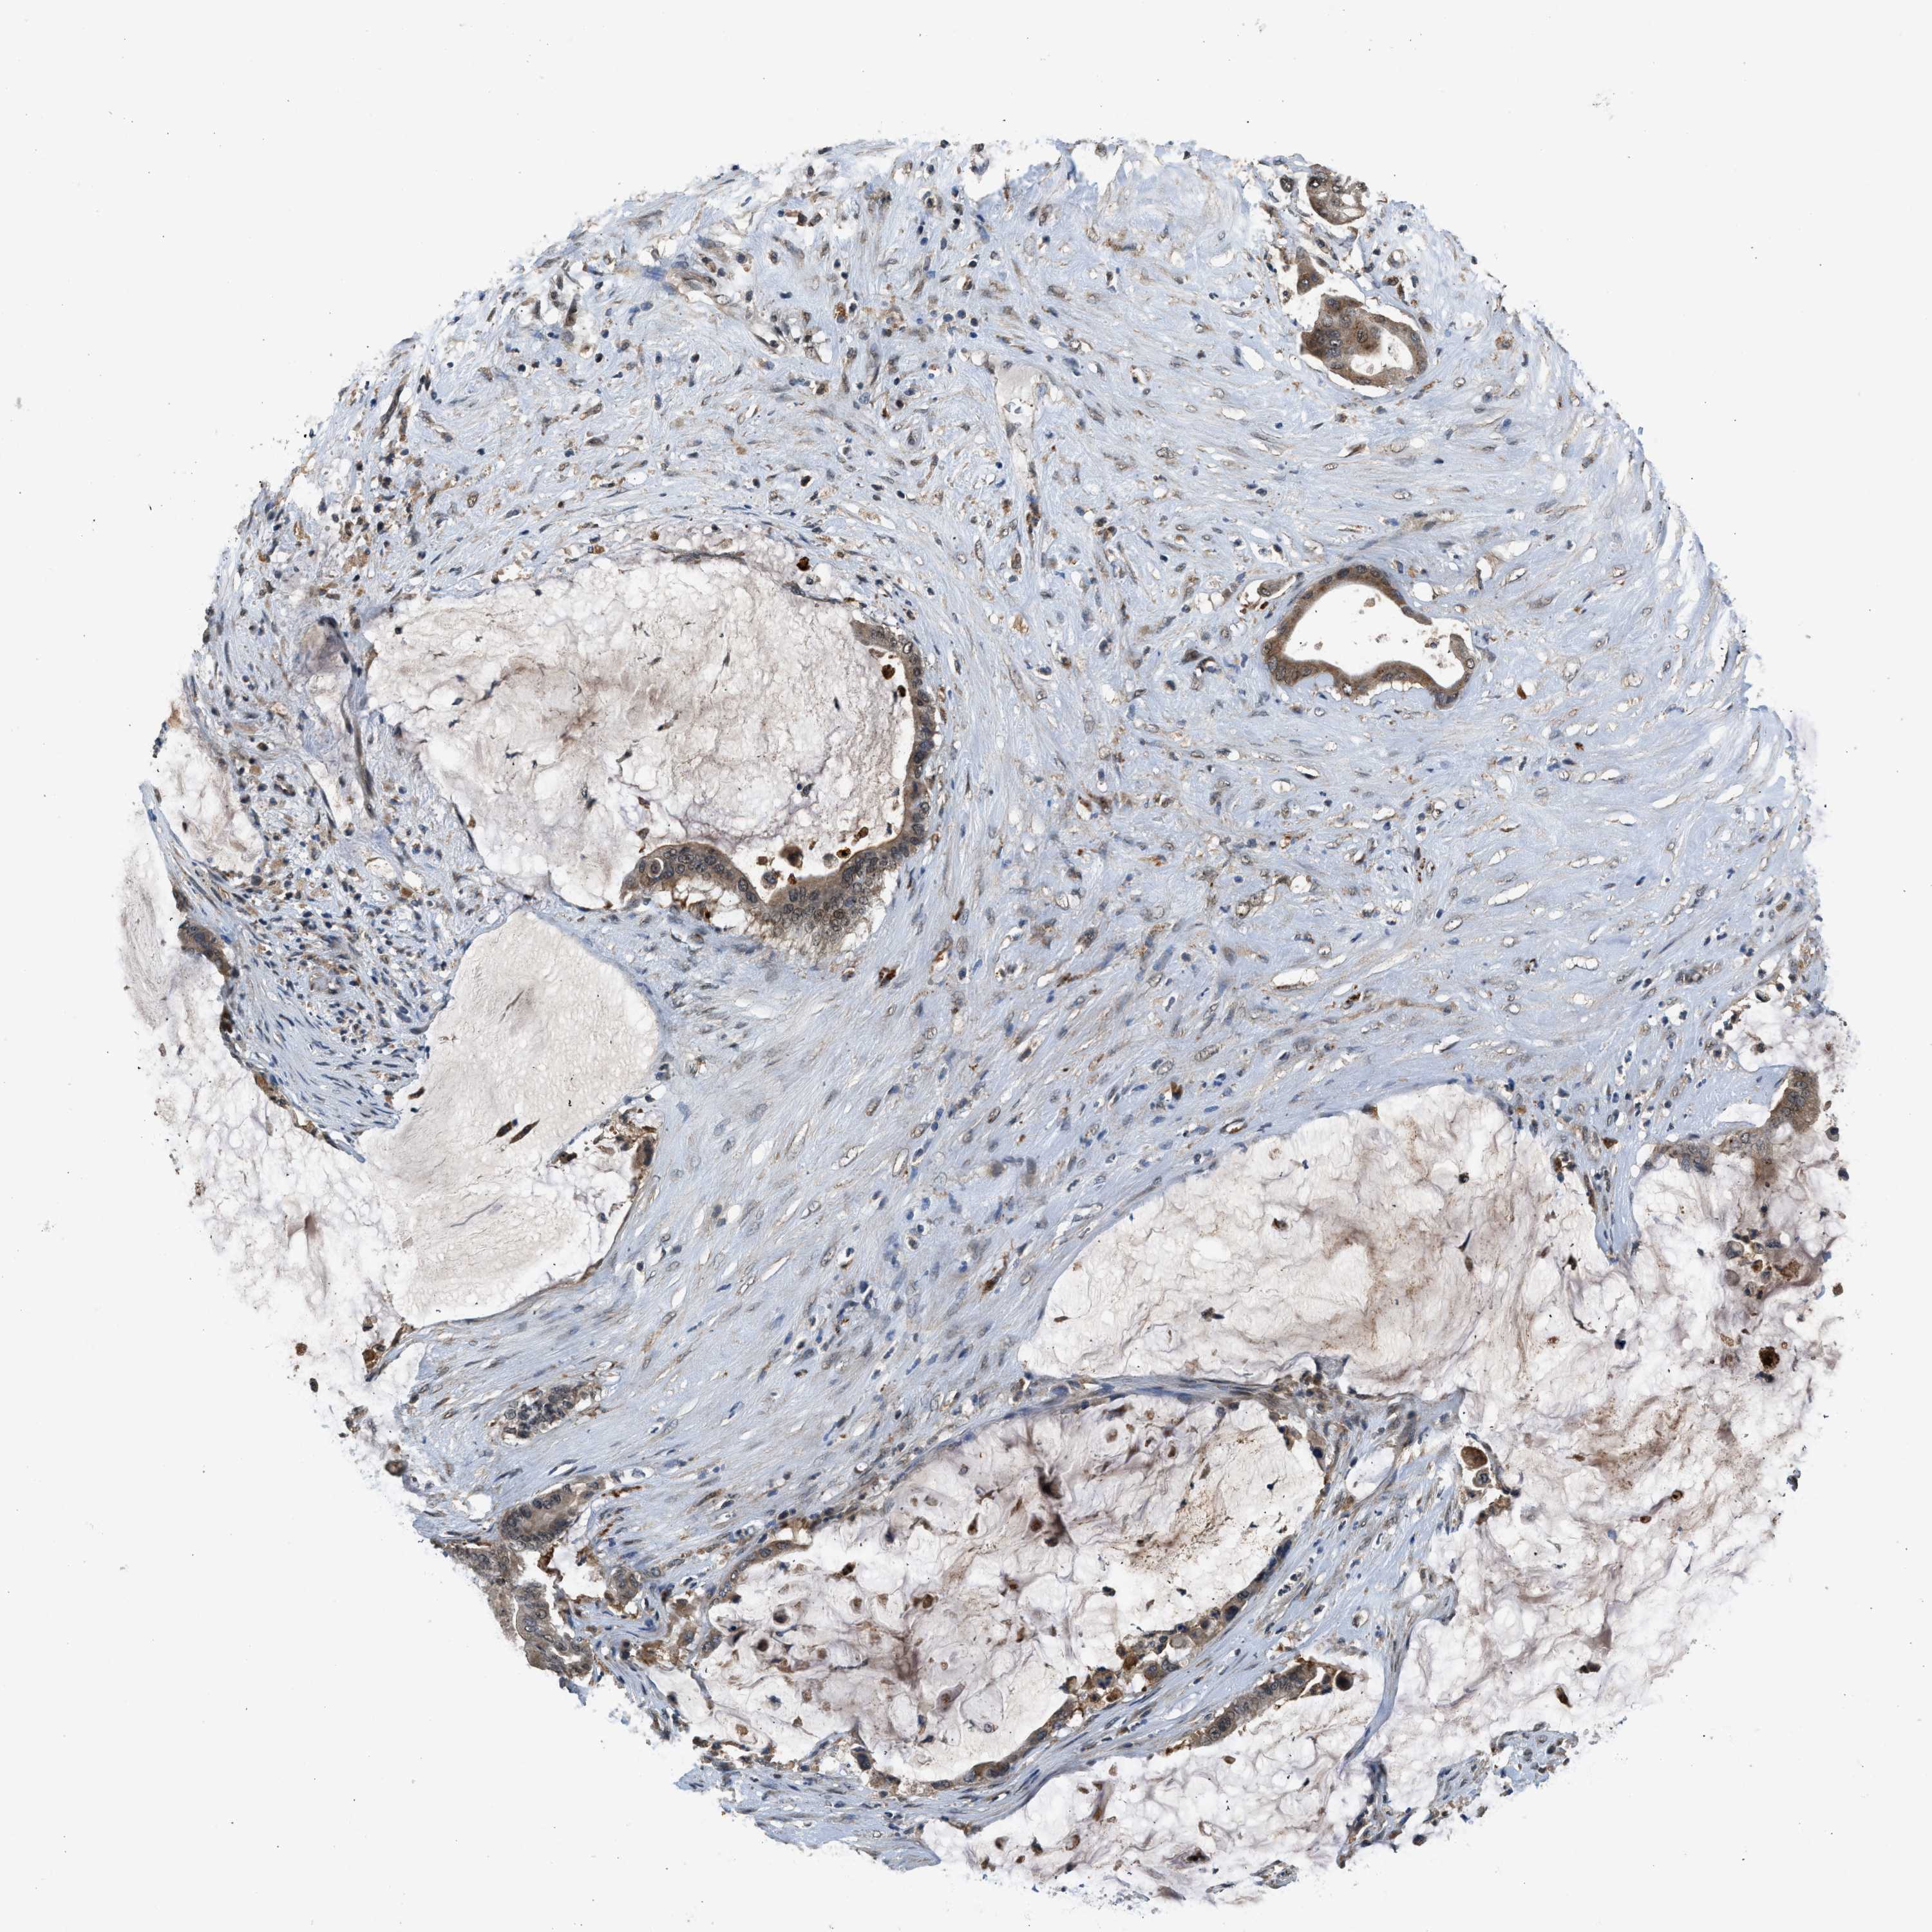

PANCREATIC CANCER - Protein expressioni

A mouse-over function shows sample information and annotation data. Click on an image to view it in a full screen mode. Samples can be filtered based on level of antibody staining by selecting one or several of the following categories: high, medium, low and not detected. The assay and annotation is described here.

Note that samples used for immunohistochemistry by the Human Protein Atlas do not correspond to samples in the TCGA dataset.

Antibody stainingi

Antibody staining in the annotated cell types in the current human tissue is reported as not detected, low, medium, or high, based on conventional immunohistochemistry profiling in selected tissues. This score is based on the combination of the staining intensity and fraction of stained cells.

Each image is clickable and will lead to virtual microscopy that enables deeper exploration of all samples and also displays staining intensity scores, fraction scores and subcellular localization as well as patient and tissue information for each sample.

Antibody HPA016713

Staining

High

Medium

Low

Not detected

Intensity

Strong

Moderate

Weak

Negative

Quantity

>75%

75%-25%

<25%

None

Location

Nuclear

Cytoplasmic/membranous

Cytoplasmic/membranous,nuclear

Adenocarcinoma, NOS